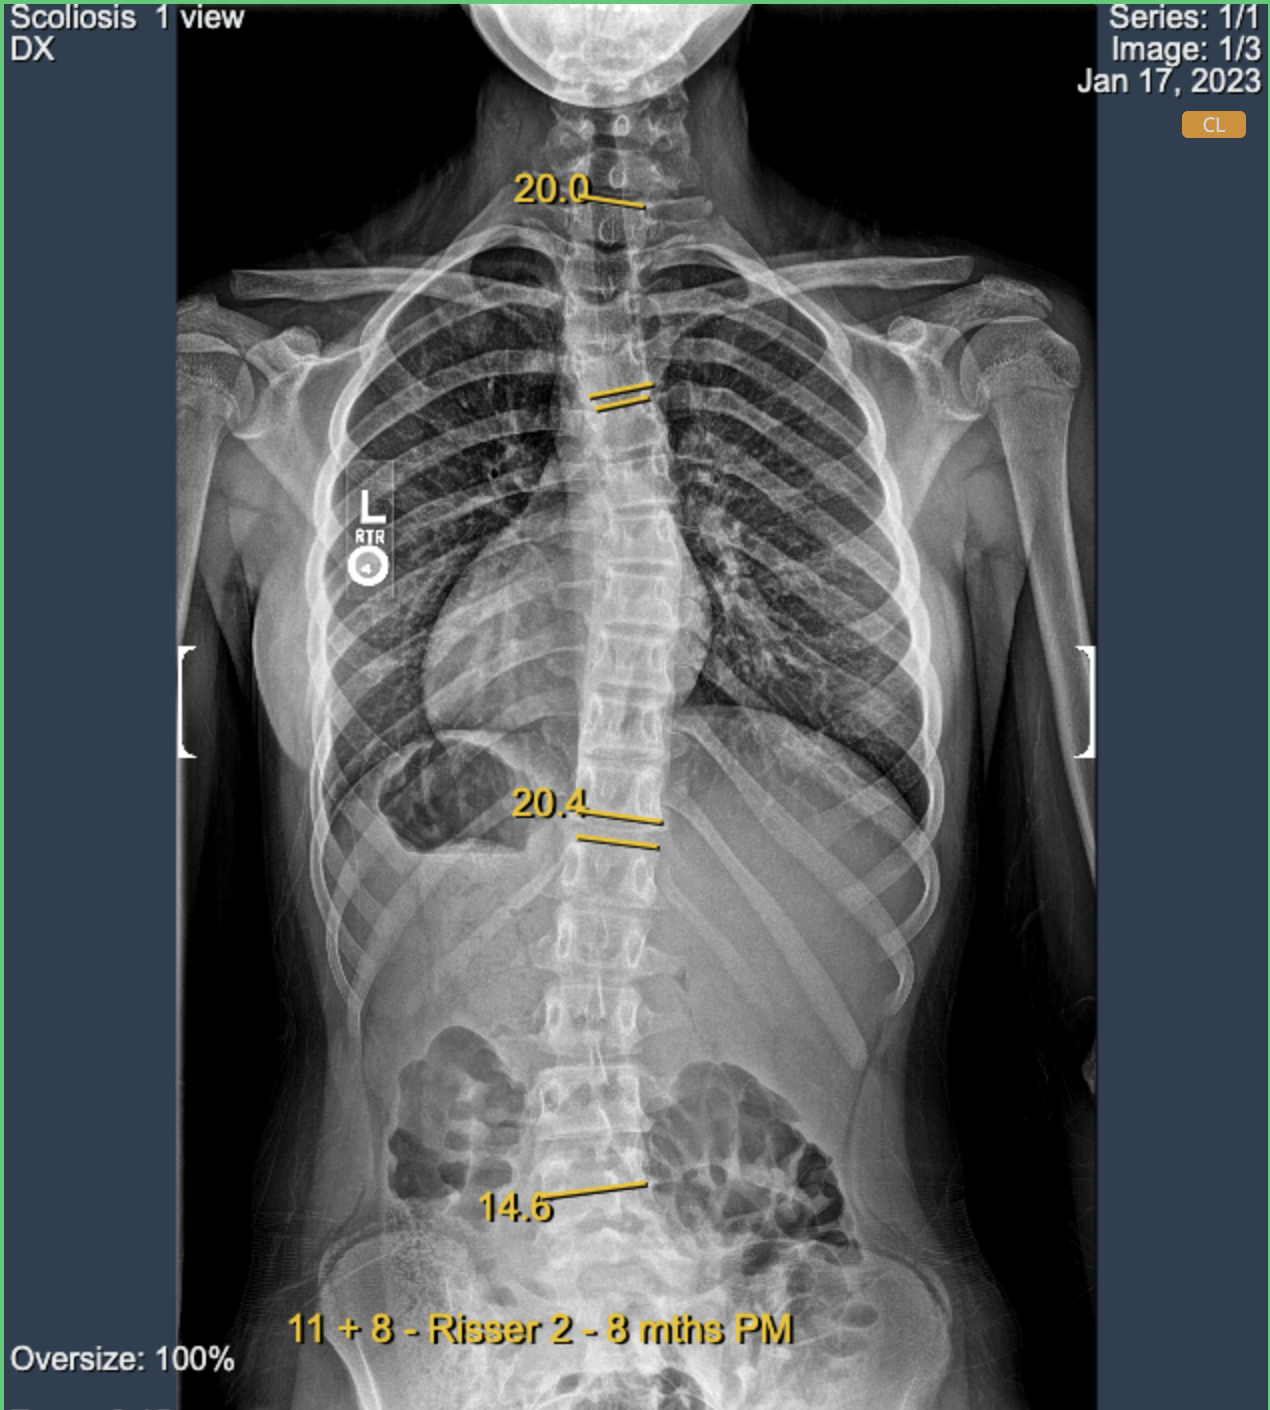

Support for DICOM graphic annotations (trial)

This enhancement supports the uploading of DICOM files (modality=PR) containing previous annotations. These images can now be displayed in eVue with the annotations from the DICOM.

This feature is still in trial phase and may not show all kind of annotations.